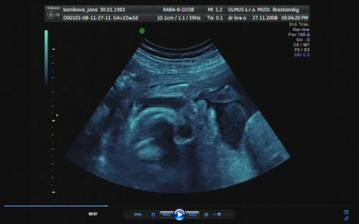

30.10.2008 - výsledky skríningových testov dopadli na jednotku, veľmi sa tešíme a dňa *****27.11.2008 - sme sa objednali na 3D ultrazvuk, tak som zvedavá, či nám potvrdia dievčatko a uvidím to na vlastné oči ... všetkým sa akosi zdá, že to bude chlapec 🙂 ....

Tak a máme to za sebou, náš 3D ultrazvuk, na ktorý sme sa moc moc tešili, bolo to úžasné, naša bambula Simonka sa nám ukázala v plnej kráse, akurát si zakrývala tváričku a nie a nie sa nám ukázať ... ale pár fotiek sa predsa len podarilo..pán doktor všetko prezrel a zatiaľ sa všetko vyvíja tak ako má .....